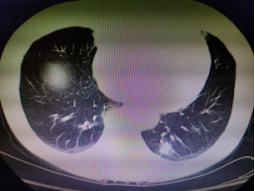

近日,一位高齡患者因體檢發(fā)現(xiàn)左下肺占位,前往我院胸心外科就診。在完善相關(guān)檢查后,評(píng)估為肺惡性腫瘤可能性極大,必須及時(shí)切除。為最大限度減少手術(shù)產(chǎn)生的不良反應(yīng),艾成決定為患者實(shí)施創(chuàng)傷小、術(shù)后疼痛輕、恢復(fù)快的單孔胸腔鏡下肺癌根治術(shù)。

術(shù)中先行肺占位楔形切除,冰凍活檢證實(shí)為“腺癌”,遂進(jìn)一步實(shí)施肺葉切除+系統(tǒng)淋巴結(jié)清掃術(shù),兩小時(shí)左右,手術(shù)順利完成,術(shù)中出血不到50ml,手術(shù)切口僅3cm,患者恢復(fù)良好。

CT提示左下肺占位直徑約20mm 手術(shù)中 單孔微創(chuàng)切口